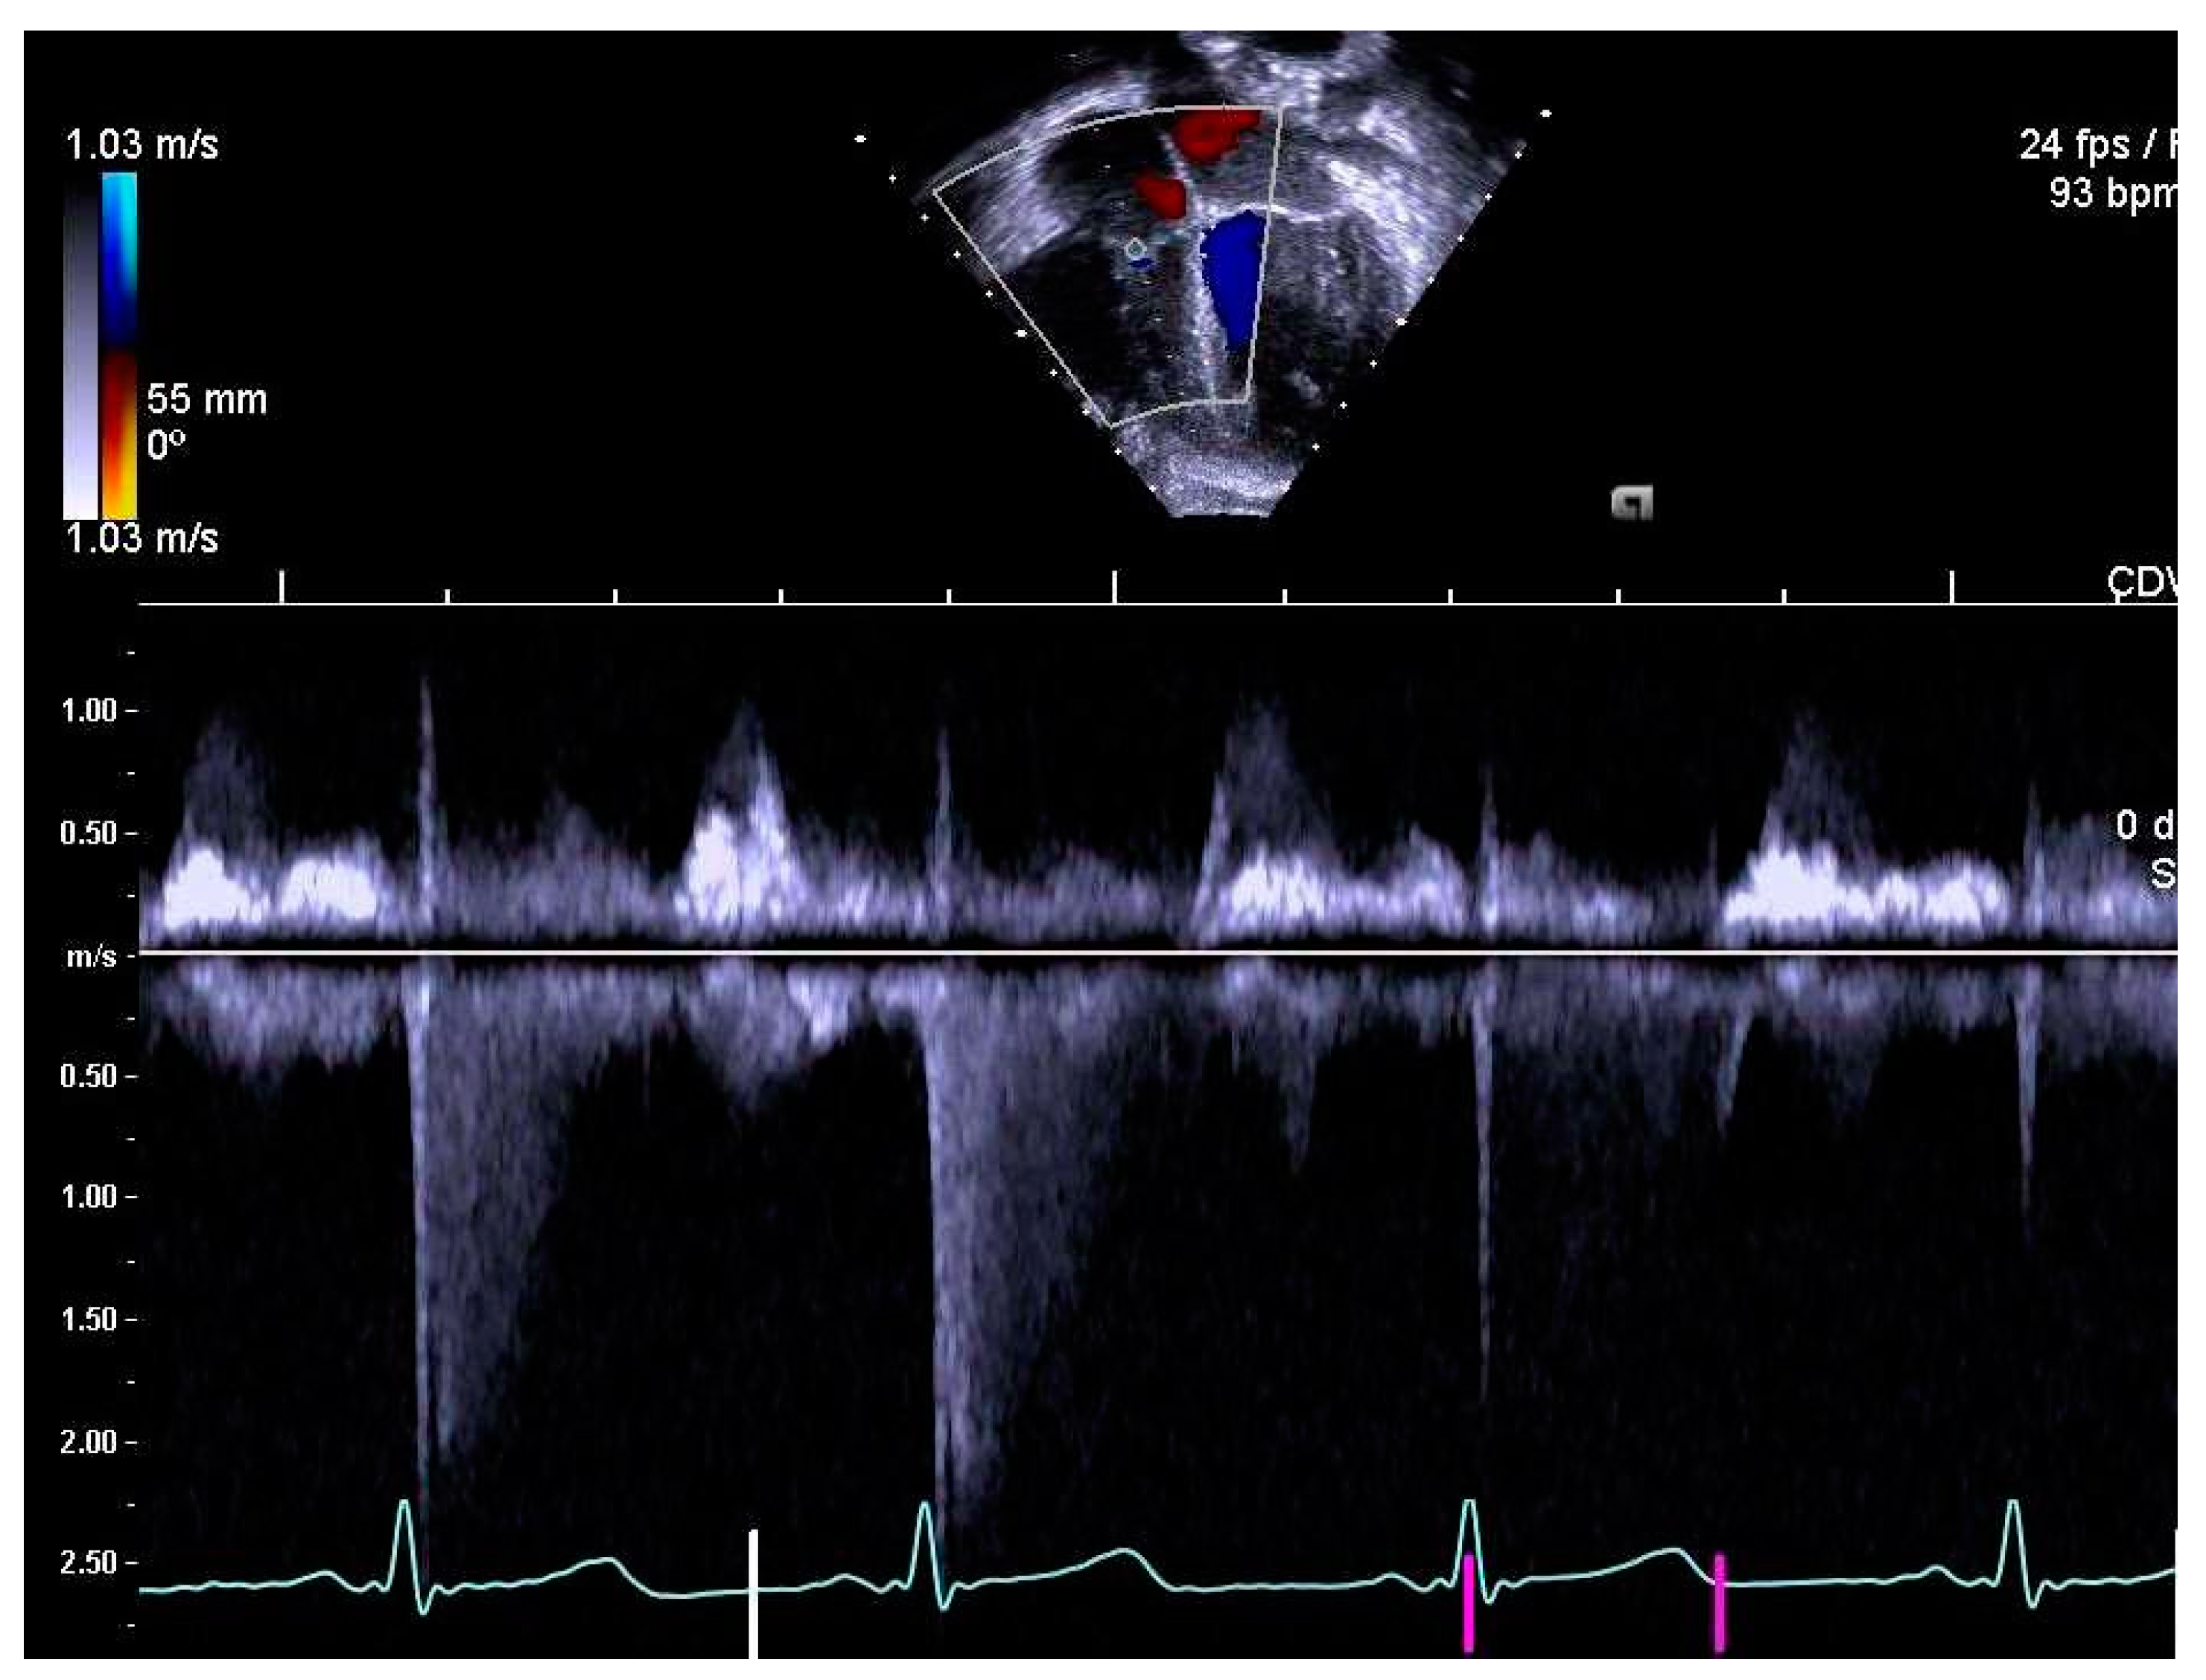

Figure 2.

Tricuspid regurgitation (TR) measured by continuous wave Doppler.

The same experienced cardiac sonographer at each centre investigated all participants and followed a predefined standardized protocol. Image analyses of the right heart and the pulmonary arteries, as well as systolic and diastolic functions acquired with 2D echocardiography and blood- and tissue Doppler, were performed off-line by two operators: one (LAM) for recordings from Stockholm and Umeå, and another (OB) for Lund. Both operators were blinded to group belonging, and vascular dimensions as well as systolic and diastolic functions were determined using similar techniques as in previously reports of the systemic arteries and left heart [9,10]. RV volumes were calculated with velocity time integral for right ventricular outflow tract (RVOTvti) estimated by pulsed wave Doppler (PW) and pulmonary valve annulus diameter (PVann), Figure 1. RV relative wall thickness (RWT) was calculated as (anterior wall + interventricular septum)/ RV width. Sphericity index (SI) was calculated as diameters for length/width for the atrium and ventricle, respectively. Pulmonary vascular resistance (PVR) was estimated by Doppler, calculating the ratio using the simplified formula described by Abbas et al. 2003, for tricuspid valve regurgitation (TR), Figure 2, divided by RVOTvti [20]. Systolic function was evaluated by tricuspid annular plane systolic excursion (TAPSE), Figure 3 and diastolic function was assessed by early (E) and late (A) velocities of the tricuspid valve with pulsed wave and, with tissue Doppler (s’, e’, a’). To estimate RV filling pressure, the E/e’ ratio was calculated. Systolic ejection time (et), isovolumic relaxation time (ivrt) and isovolumic contraction time (ivct) were assessed with tissue Doppler to calculate right ventricular myocardial performance index (RVmpi’), using the formula (ivrt + ivct)/et, Figure 4.

PVR was significantly higher in EXPT than in CTRL and according to the limit of TR/RVOTvti > 0.2 for PVR > 2 Woods units (WU), 32% of EXPT children and 16% of CTRL children exceeded this limit [21]. However, one EXPT child and one CTRL child had an indication of pulmonary arterial hypertension > 6 WU, i.e., a ratio of tricuspid regurgitation to velocity time integral of right ventricular outflow above the cut-off of 0.275 [22].